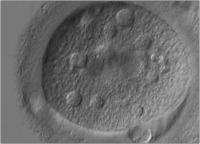

Die Bedeutung der Morphologie der Oozyte hinsichtlich ihres weiteren Entwicklungspotentials

Journal für Reproduktionsmedizin und Endokrinologie - Journal of Reproductive Medicine and Endocrinology 2006; 3 (1): 17-23 Volltext (PDF) Summary Abbildungen